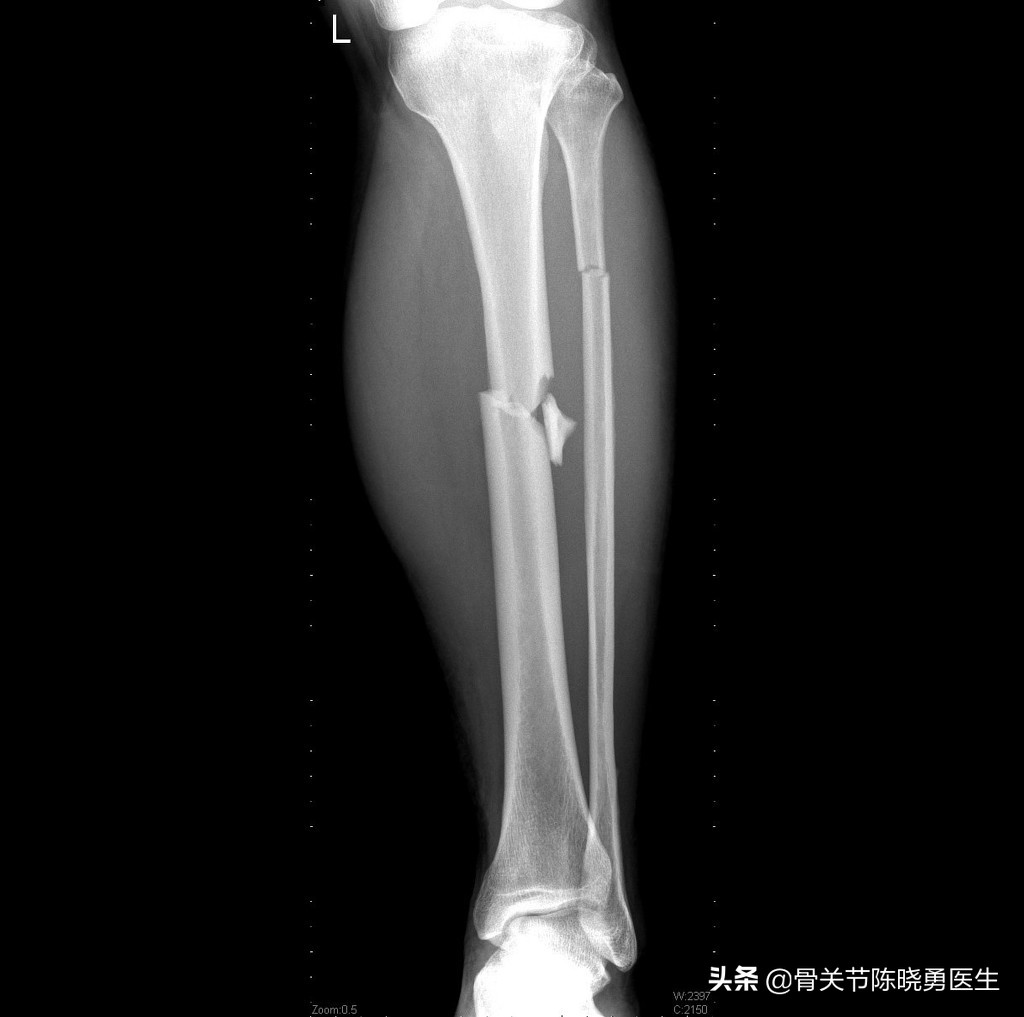

腓骨和胫骨干骨折

车祸、运动损伤或跌倒可能导致损伤踝关节上方的胫骨和腓骨同时损伤,这种损伤又被称为“胫腓骨骨折”。这种骨折通常需要手术来恢复下肢的正常力线。

当对胫骨进行手术固定以后,如果医生评估腓骨骨折不会影响下方的踝关节,就不需要对腓骨进行固定。

也有少数病例的胫腓骨骨折没有发生明显移位,此时可以考虑采用长腿石膏(大腿到脚)对骨折进行支撑和保护。